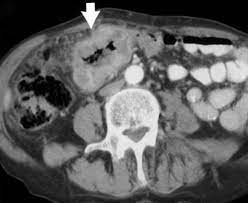

Can Cat Scan Find Colon Cancer - Scielo Brasil Differentiation Between Stercoral Perforation And Colorectal Cancer Perforation Differentiation Between Stercoral Perforation And Colorectal Cancer Perforation / Often the doctor will recommend a ct scan for a detailed examination of internal organs such as the large.. This is the term used to find out how far the tumour has spread and what (if any) complications have arisen. Computed tomography (ct or cat) scan. Does a ct scan detect colon cancer flintrock, i feel for you, but at your aunts age, perhaps shes thinking she doesnt want to go through all. A ct scan may see irregularities in the liver that may be malignant. Routine colonoscopies can find colon cancer in its early stages.

The images often help doctors find out if they can remove the tumor through surgery or if it has metastasized (spread to. Can ct scan detect colon cancer? Because colorectal cancer often bleeds into the large intestine or rectum, people with the disease may become anemic. Preparation before test lab ct scan procedures. It occurs both in men and in women.

Can ct scan detect colon cancer? Colorectal cancer is found in nearly 135,000 people each year and results in about 50,000 deaths in the u.s. What happens before the cat scan? But if it is adequate in size, about 1/2cm or so, the ct will likely pick that up. Ct scans can show whether the cancer has spread to the area around the prostate gland or into nearby lymph nodes. A ct scan may see irregularities in the liver that may be malignant. Colon cancer develops when tumorous growths develop in the large intestine. Ct scans help doctors diagnose and treat medical conditions such as pancreatic cancer. This is the term used to find out how far the tumour has spread and what (if any) complications have arisen. It occurs both in men and in women. Cancer of the pancreas is rarely diagnosed until it is in the final stages, which is why yes, it can. Metastatic colon cancer can be treated with chemotherapy, which is known to be the standard treatment for metastatic colon cancer, apart from chemotherapy, treatments like radiation therapy and targeted therapy can also be. Find out about symptoms and risk factors for colon cancer, also called colorectal cancer.

Colon Cancer Ct Scan Stock Image C047 9257 Science Photo Library from media.sciencephoto.com This screening test allows your doctor to carefully examine your colon for signs of polyps (abnormal growths on the inside surface of the colon that below, you can learn about the different types of screening tests for colorectal cancer. What are hereditary colon cancer syndromes? Knowing this helps you and your doctor choose the best treatment options. Ct scanners first began to be installed in 1974. It usually begins as small, noncancerous (benign) clumps of cells called. Feline cancer initially manifests as a lump or bump on any parts of the body. Ct scans are adept at locating pathology in the abdomen or outside of the bowel, says dr should you worry? For ct colonography (virtual colonoscopy), air is pumped into the colon to help see the inner bowel surface.

Imaging Of Colorectal Cancer The Clue To Individualized Treatment from www.degruyter.com Staging tests may include imaging procedures such as abdominal, pelvic and chest ct scans. Ct scan result colon cancer staging. Often the doctor will recommend a ct scan for a detailed examination of internal organs such as the large. A ct scan can often detect evidence of a growth or tumor. Colon cancer refers to cancer diseases that occur in the large and small intestine. If my own mother asked me what she should do to prevent colon cancer, i would tell her to this test is essentially a cat scan of the colon, designed to find large polyps and cancers. Find out about symptoms and risk factors for colon cancer, also called colorectal cancer. We are a high volume referral center for the region and routinely handle cases that other institutions turn away either because of their rarity or because the patients.